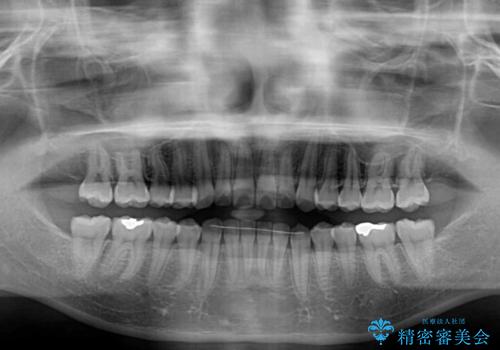

- 上下前歯のデコボコと、上顎前歯の突出感を気にして来院された患者様です。

インビザラインによる上下歯列の側方拡大と後方移動、IPR(歯と歯の間を削る)にるスペースの獲得により歯列を整えることとしました。

毎日22時間以上しっかりとマウスピースを装着していただいたので、スムーズに治療が進みました。歯と歯の間を削ることでうまくスペースコントロールでき、1年強で終えることができました。